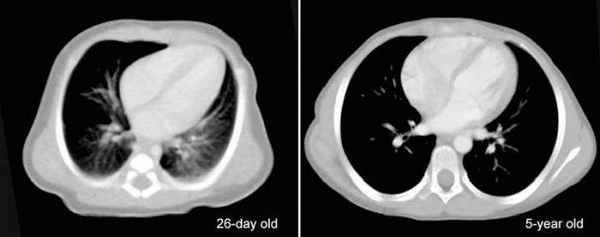

Изобретение относится к медицине, функциональной диагностике. Одновременно регистрируют звуковую деятельность внутренних органов с помощью 4 и более микрофонов, расположенных на поверхности тела пациента. Сравнивают разницу во времени между приходом звуковых волн от источника звука в разные точки ее регистрации. Способ позволяет определить пространственную локализацию источника звука и обнаружить кардиологические заболевания. 1 ил.

Поставленная задача достигается при одновременной регистрации звуковой деятельности внутренних органов с помощью нескольких (4 или более) микрофонов, расположенных на поверхности тела пациента, и последующем математическом анализе полученных результатов с помощью ЭВМ. Сравнивается разница времени между приходом звуковых волн от источника аускультативного феномена в разные точки регистрации звуковой деятельности для определения пространственной локализации источника звука.

Способ диагностики кардиологических заболеваний с помощью трехмерной фонокардиографии осуществляется следующим образом: у пациента одновременно в различных точках аускультации с помощью специальных микрофонов регистрируется звуковая деятельность исследуемого органа, проводится высокоточное аналогово-цифровое преобразование звукового сигнала и передача информации в ЭВМ для последующей обработки и визуализации результатов.

Аппаратно-программный комплекс, выполняющий поставленную задачу, должен состоять из 5 частей: 4 или более высокочувствительных микрофонов, высокоточного аналогово-цифрового преобразователя, высокоскоростной шины для передачи оцифрованного сигнала в ЭВМ и высокопроизводительного компьютера, на котором установлена специально созданная программа для диагностики звуковой деятельности внутренних органов.

Для точного определения в пространстве источника звуковой деятельности необходимо располагать информацией по меньшей мере с 4 микрофонов. Согласно закону распространения звука в пространстве, при использовании одного микрофона и получении звукового сигнала от источника звуковой деятельности, даже если известно расстояние от микрофона до источника звука, он может располагаться на любой точке геометрической фигуры - сферы, в центре которой располагается микрофон. При использовании двух микрофонов вероятными точками для каждого микрофона будут точки, расположенные на окружности, полученной при взаимном пересечении двух сфер, соответствующих возможным точкам для каждого из микрофонов. При использовании трех микрофонов и анализе разницы времени прихода звуковой деятельности в три микрофона, вероятными точками будут две, получаемые при пересечении окружности, полученной взаимным пересечением двух сфер от первых двух микрофонов сферой, соответствующей подмножеству точек третьего микрофона.

Именно поэтому для точной топической диагностики источника звука в пространстве необходимо применение не менее четырех микрофонов.

На чертеже представлена схема одной из методик расчета пространственного расположения источника звука при помощи четырех микрофонов.

Точки расположения микрофонов принимаем за Ml, М2, М3 и М4; среднюю скорость распространения звука в тканях за Vcp; точку, соответствующую источнику звука - З; время задержки звуковой волны при достижении звука точек М2, М3 и М4 по сравнению с приходом волны в точку Ml принимаем за Т2, Т3 и Т4; точку, соответствующую приходу звуковой волны к самому близкому микрофону Ml, принимаем за R1; точки, которые проходит звуковая волна в момент достижения самого близкого микрофона M1 на отрезках, соединяющих источник шума с остальными микрофонами, принимаем за R2, R3 и R4.